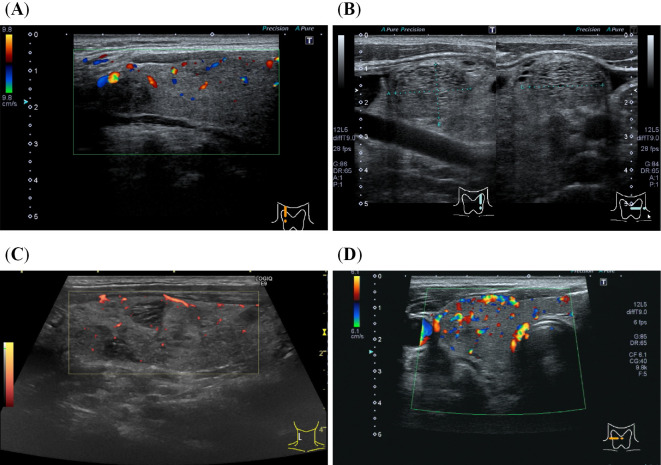

碘过量会影响甲状腺的病理生理学以及各种甲状腺相关检查的结果。我们在此报告了一名患有甲状腺毒症和碘过量的 60 岁日本男子,其原因是 20 年来习惯性使用聚乙烯吡咯烷酮碘(PVP-I)漱口。最初的实验室和影像学检查结果提示为无痛性甲状腺炎。然而,在停止使用聚乙烯吡咯烷酮碘漱口后,这些结果转变为提示巴塞杜氏病的结果,并且甲状腺毒症不断恶化。即使是生活在碘充足地区的患者,由于碘引起的甲状腺毒症也很少见,因此有关碘过量的详细问卷对于准确诊断甲状腺毒症非常重要。

Excess iodine can influence the pathophysiology of the thyroid gland and results of various thyroid-related examinations. We herein report a 60-year-old Japanese man with thyrotoxicosis and excess iodine due to habitual use of polyvinylpyrrolidone iodine (PVP-I) to gargle for 20 years. Initial laboratory and imaging findings were suggestive of painless thyroiditis. However, after cessation of PVP-I use for gargling, these results changed to findings suggestive of Graves' disease, with worsening thyrotoxicosis. A detailed questionnaire regarding excess iodine is important for the accurate diagnosis of thyrotoxicosis, even in patients living in iodine-sufficient areas where iodine-induced thyrotoxicosis is rare.